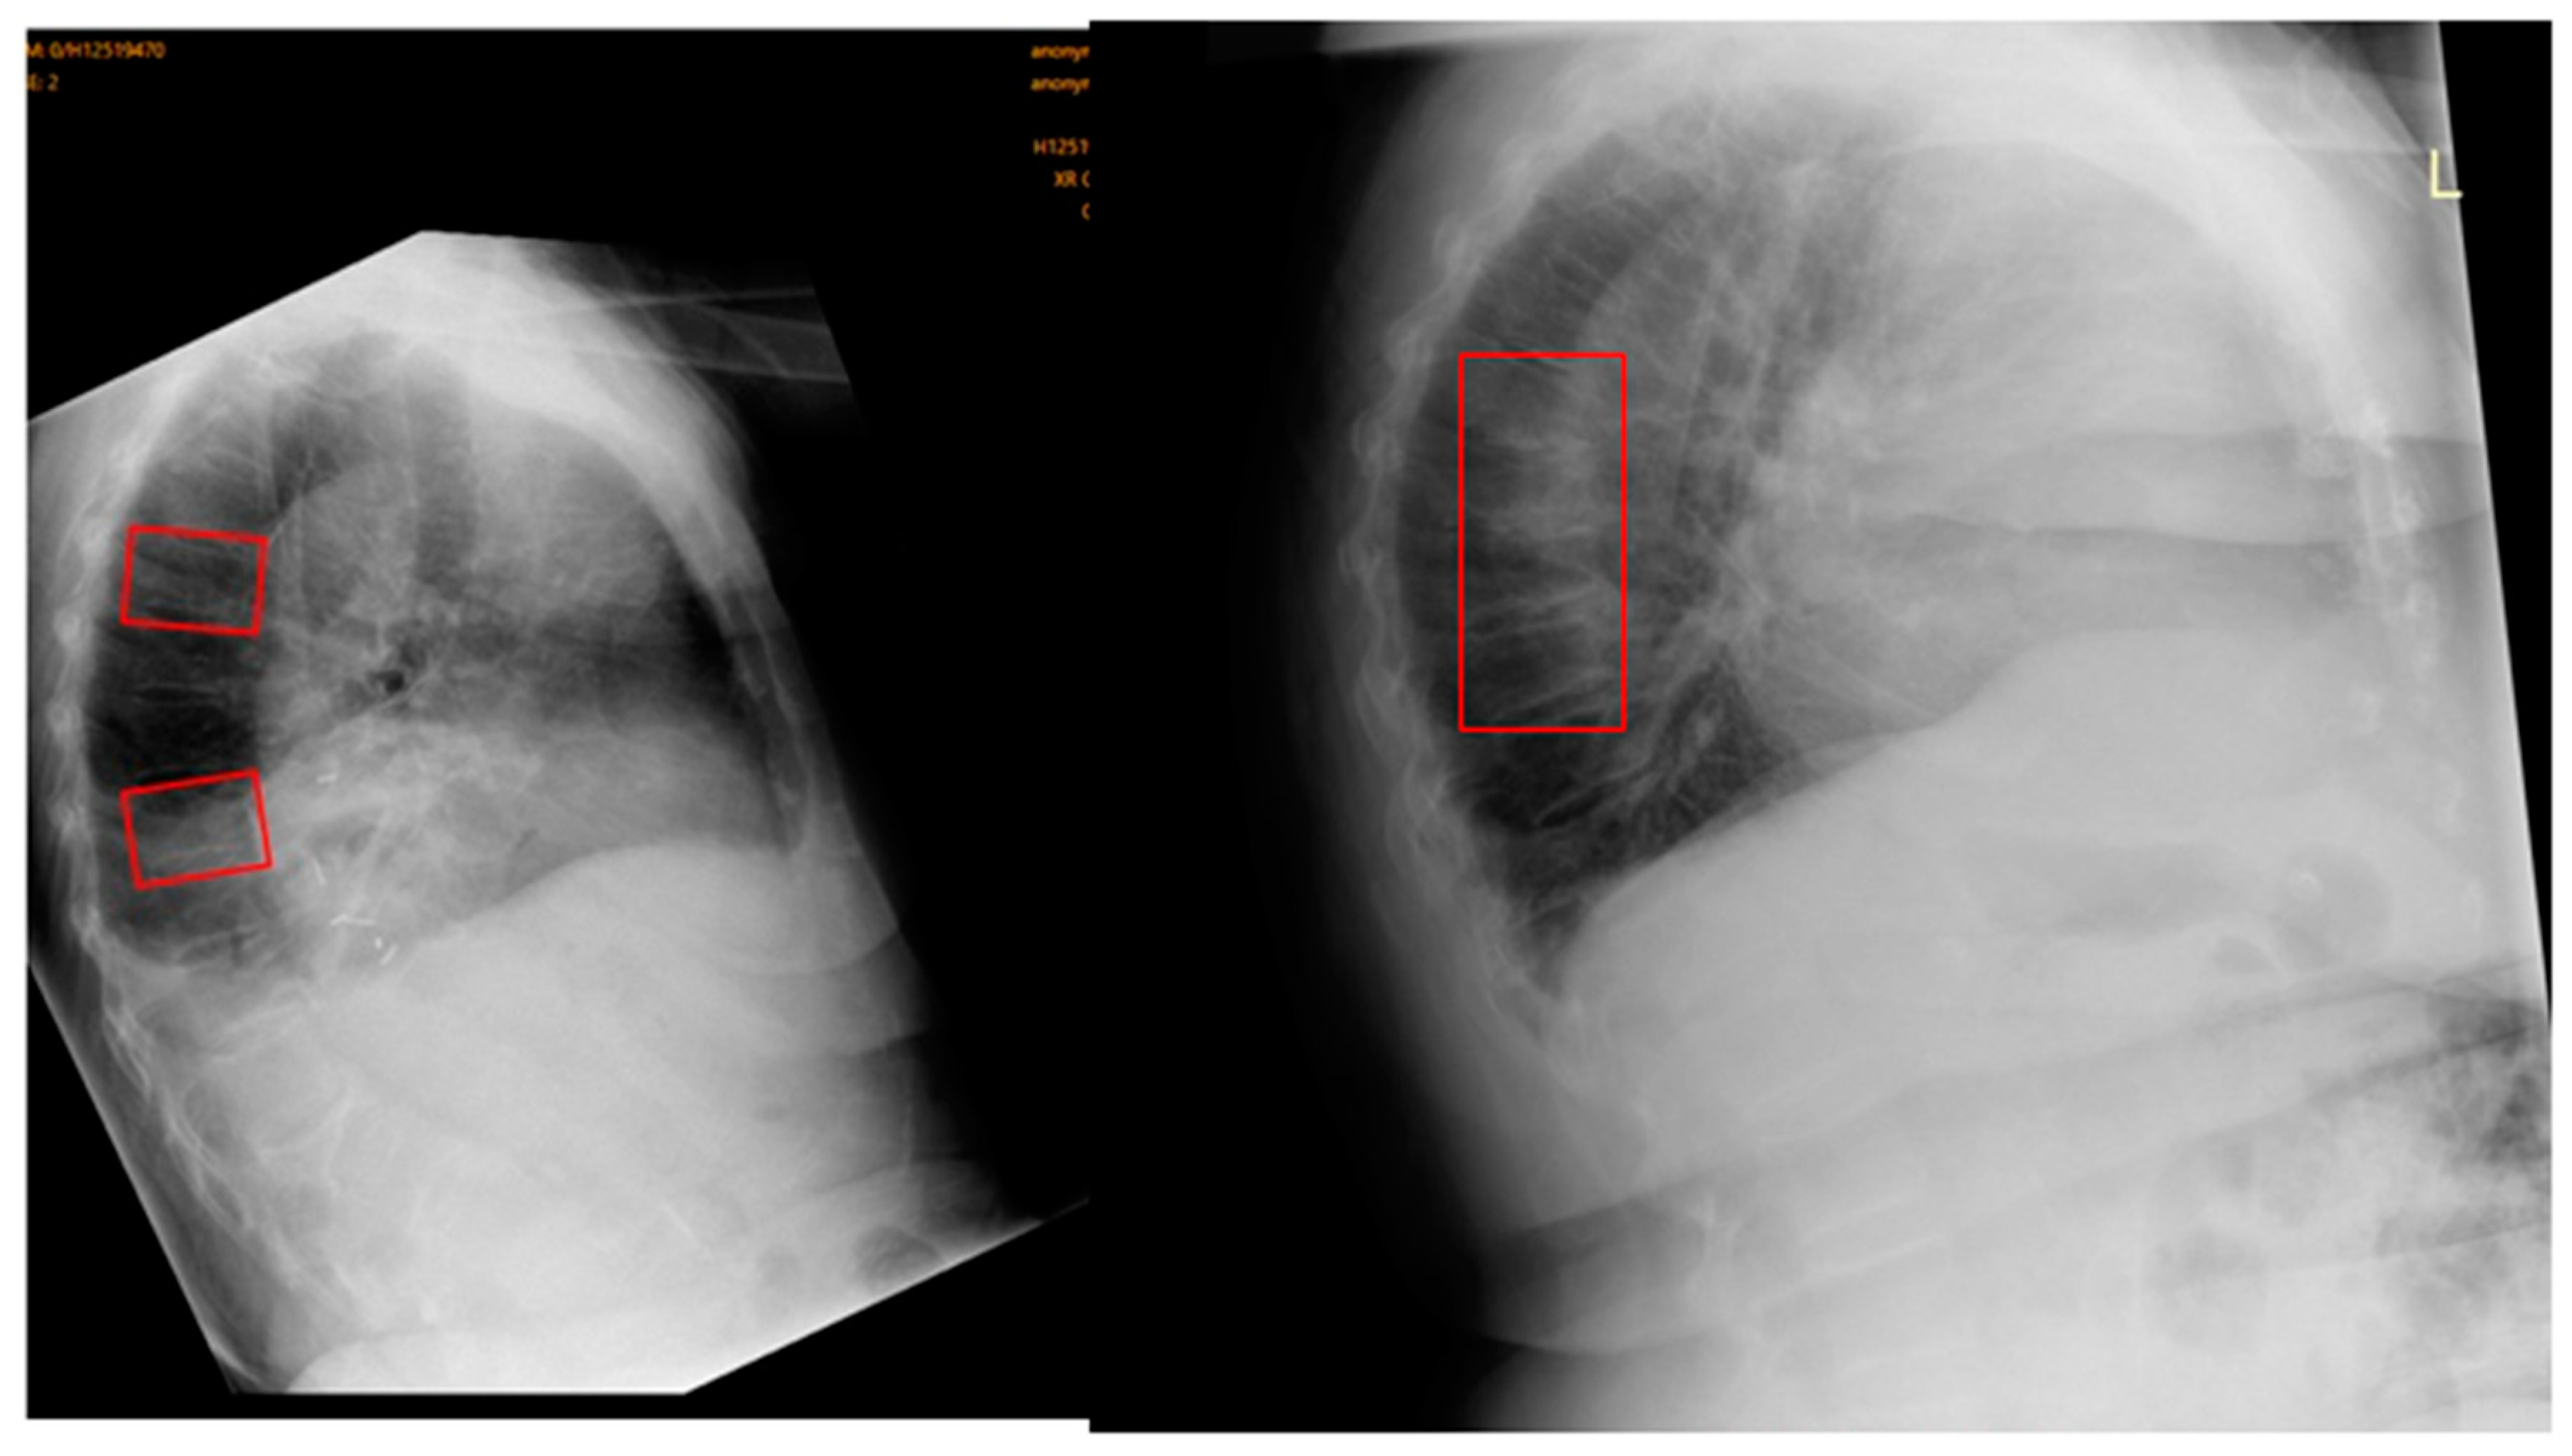

Figure 6. OVFs in different cases that were detected by the AI but missed by the original radiologist reports.